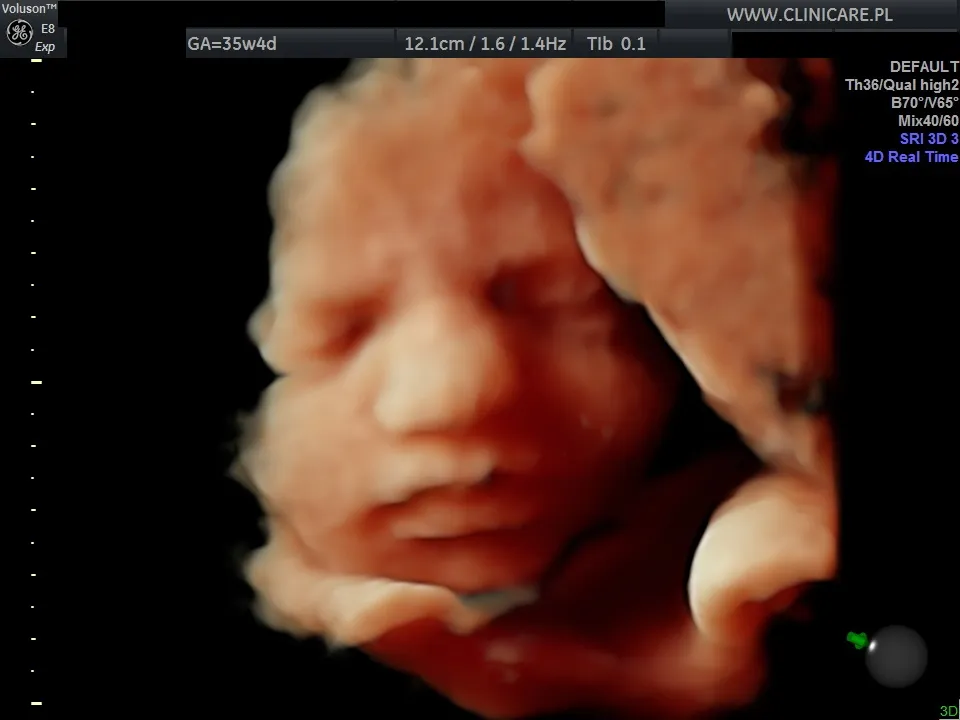

Trzecie badanie prenatalne to ważny etap w opiece nad rozwijającym się dzieckiem, szczególnie w ostatnich tygodniach ciąży. Pozwala ono na precyzyjną ocenę dobrostanu malucha i jest kluczowe dla przyszłych rodziców, którzy pragną mieć pewność co do zdrowia swojego dziecka. W tym artykule odpowiemy na kluczowe pytanie: kiedy dokładnie należy wykonać to badanie, a także szczegółowo wyjaśnimy, co dokładnie ocenia lekarz podczas tej wizyty.

Trzeci trymestr ciąży to okres intensywnego wzrostu i rozwoju dziecka, a także przygotowań organizmu do porodu. W tym czasie znaczenie monitorowania stanu zdrowia płodu wzrasta, a właśnie trzecie badanie prenatalne odgrywa kluczową rolę w ocenie jego dobrostanu. Dzięki niemu możemy upewnić się, że dziecko rozwija się prawidłowo i jest gotowe na przyjście na świat.

Podczas gdy badania prenatalne w pierwszym i drugim trymestrze skupiały się głównie na ocenie ryzyka wad genetycznych oraz wczesnym wykrywaniu wad rozwojowych, trzecie badanie prenatalne ma nieco inny priorytet. Koncentruje się ono przede wszystkim na ocenie wzrastania płodu, monitorowaniu jego dobrostanu w zaawansowanej ciąży oraz wykrywaniu ewentualnych wad rozwojowych, które mogły ujawnić się lub stać się widoczne dopiero w późniejszym etapie. To przesunięcie akcentu jest naturalne, ponieważ dziecko jest już na tyle rozwinięte, że można ocenić jego kondycję przed porodem.

Wyniki trzeciego badania prenatalnego mogą przynieść przyszłym rodzicom nieoceniony spokój i pewność. Wiedza o tym, że dziecko rośnie prawidłowo, jego narządy rozwijają się właściwie, a jego położenie jest odpowiednie do porodu, pozwala z większą ufnością oczekiwać na rozwiązanie. Dodatkowe informacje o stanie łożyska i ilości płynu owodniowego są równie istotne dla bezpiecznego planowania porodu. To wszystko składa się na poczucie kontroli i przygotowania do tak ważnego momentu.